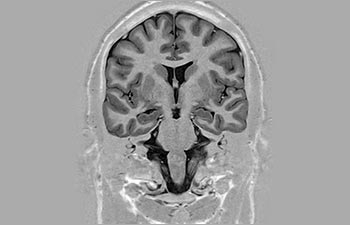

Enhanced diagnostic confidence in neuro oncology